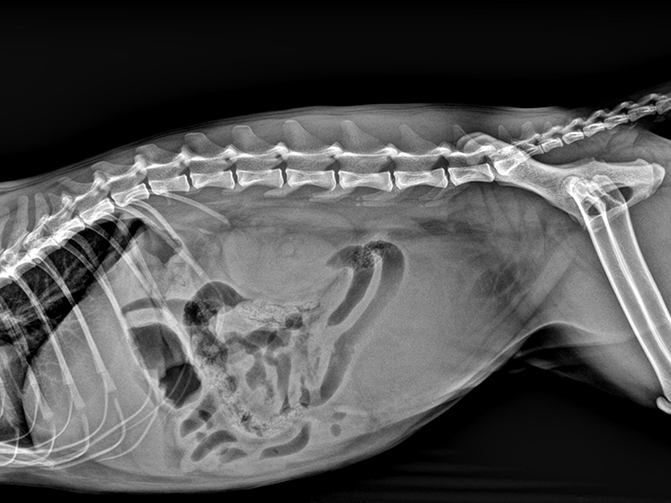

微焦点球管、微像素平板探测器以及高级图像处理算法是获取优越图像的黄金搭档,实现精准成像,提高病灶检出率。

舒博尔XVIEW-体化图像采集处理软件,具有强大的图像算法处理能力和人性化的操作流程,从登记-拍摄部位选择、采集处理图像、报告打印输出一气呵成,智能的动物解剖部位预设程序,可以根据动物类型、部位、体型自动调出高压曝光参数,使曝光参数的选取变得非常简单。图像处理算法根据不同的动物的组织密度差异进行了细分处理,确保各种动物拍摄均能获取优异的图像质量,专业的辅助诊断测量。I具包含VHS (脊柱心脏评分)等,极大的帮助医生进行病患诊断。